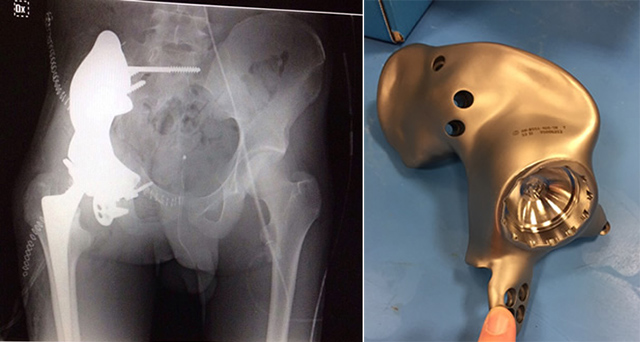

Per la prima volta al mondo una persona malata di cancro alle ossa è stata salvata grazie alla sostituzione di parte del bacino con un emibacino artificiale in titanio. L’operazione è stata svolta al Centro Traumatologico Ortopedico di Torino per risolvere un caso di osteosarcoma al bacino di un ragazzo di 18 anni, che negli ultimi mesi era stato sottoposto a 16 cicli di chemioterapia per provare a fermare il tumore. I trattamenti non avevano dato gli esiti sperati, spingendo i medici a tentare una soluzione alternativa: rimuovere i tessuti ossei ormai compromessi dalle cellule tumorali e sostituirli con una copia di parte del bacino realizzata in titanio.

Mentre il paziente proseguiva con la chemioterapia, i chirurghi del CTO hanno realizzato una TAC del suo bacino. Dalle immagini ottenute è stato possibile creare al computer un modello tridimensionale della parta interessata dal tumore. I dati sono stati inviati a una azienda negli Stati Uniti che ha realizzato l’emibacino in titanio, rivestendolo poi con tantalio, un materiale che favorisce l’integrazione delle protesi con le ossa umane.

Martedì 24 febbraio il paziente è stato sottoposto ad anestesia e in seguito è iniziato un intervento che nel complesso è durato 11 ore e mezza. I chirurghi hanno dovuto rimuovere la parte destra del bacino e l’anca, interessate entrambe dall’osteosarcoma. Poi hanno ripulito i margini delle ossa e successivamente hanno ricostruito le parti mancanti con le protesi in titanio e tantalio.

Foto: CTO di Torino